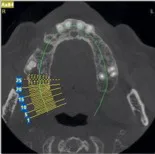

• Les différents clichés : possibilités et limites, avantages et inconvénients

• Diagnostic : du quotidien à l’exceptionnel